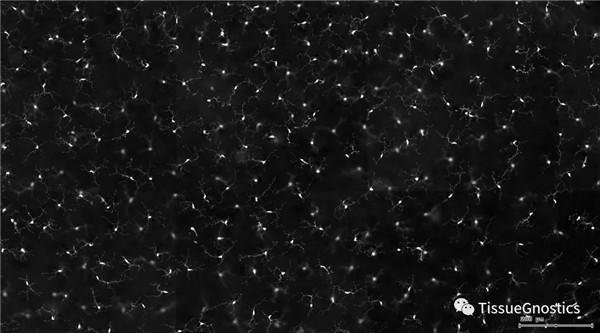

單通道灰階圖(↑:FITC,↓:Texa Red)

根據(jù)染色強(qiáng)度,染色面積,細(xì)胞形態(tài)學(xué),利用正反向回溯功能和設(shè)門圈選Gating,排除雜質(zhì),細(xì)胞碎片,黏連細(xì)胞(綠色框線標(biāo)記),獲得神經(jīng)元胞體,(粉色框線標(biāo)記),并將胞體按照面積分為兩類(散點(diǎn)圖)。